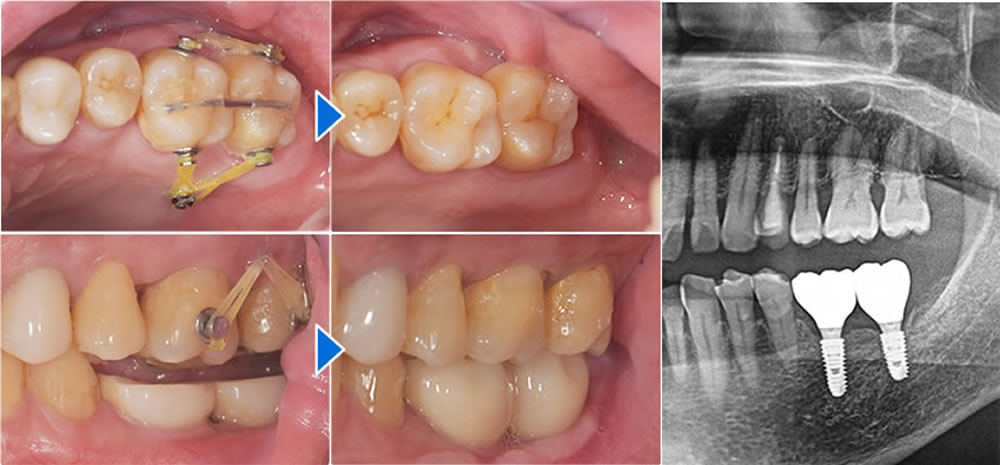

左下の歯が長期間なかったため、上の歯が伸びてきてしまっていました。適切な咬み合わせにするため、歯を削る事なく左下インプラント埋入後に矯正にて圧下し、上下バランスの良いインプラント上部構造が装着可能となりました。

(Dr姫野による矯正のためのアンカーインプラント埋入、Dr櫻井による矯正)